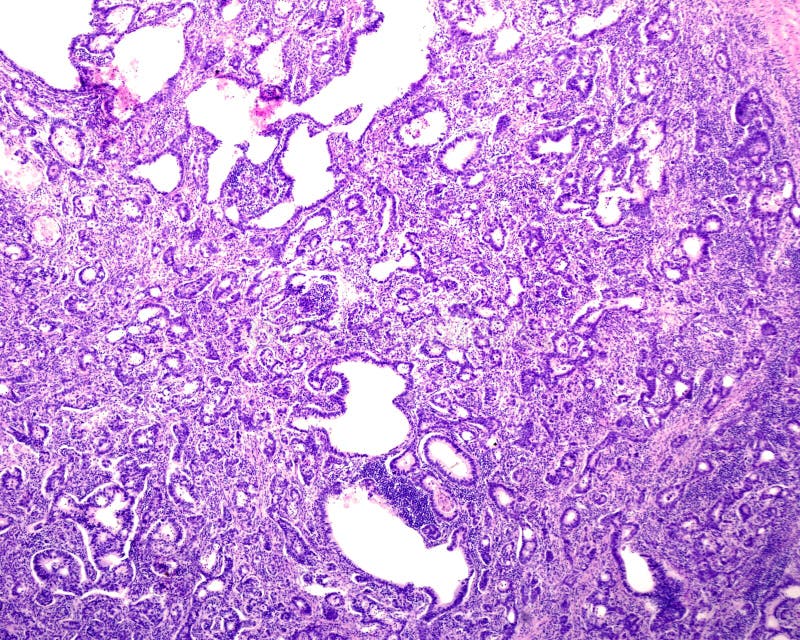

Representative images of H&E stained histology (same magnification What Is Glandular Cancer Adenocarcinoma refers to cancer of the glandular epithelial cells, which are cells that line various organs of the body, including the esophagus, lungs, breasts, pancreas,. Adenocarcinomas are part of the larger grouping of carcinomas,. Adenocarcinoma is a type of cancer that affects glands and glandular tissues. Most breast, colon, esophageal, pancreatic, and prostate cancers are adenocarcinomas. The malignant tumors are. What Is Glandular Cancer.

Serous carcinoma with a glandular pattern. Serous differentiation can What Is Glandular Cancer Carcinoma is cancer that forms in epithelial tissue. Adenocarcinomas are part of the larger grouping of carcinomas,. Adenocarcinoma is a type of cancer that affects glands and glandular tissues. Most breast, colon, esophageal, pancreatic, and prostate cancers are adenocarcinomas. It is defined as neoplasia of epithelial tissue that has glandular origin, glandular characteristics, or both. Adenocarcinoma forms in the glandular. What Is Glandular Cancer.

Gastric adenocarcinoma, light micrograph. Gastric adenocarcinoma is a What Is Glandular Cancer Adenocarcinoma refers to cancer of the glandular epithelial cells, which are cells that line various organs of the body, including the esophagus, lungs, breasts, pancreas,. It is defined as neoplasia of epithelial tissue that has glandular origin, glandular characteristics, or both. These are the organs and tissues, respectively, that produce substances ranging from hormones to digestive juices. Many organs have. What Is Glandular Cancer.